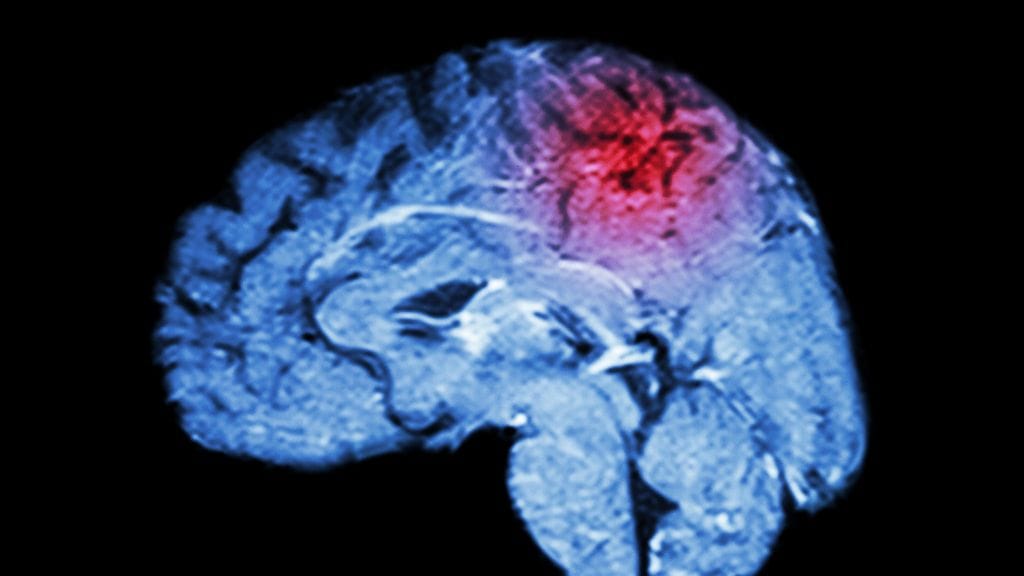

Aivoinfarktit hoidetaan liuotushoidolla, mutta osalla potilaista parempi vaihtoehto voisi olla trombektomia eli verisuonitukoksen mekaaninen poistaminen. Trombektomia on tavanomaista hoitoa parempi potilailla, joiden tukos on suuressa aivovaltimossa, tuore katsaustutkimus osoittaa.

Tukoksen mekaaninen poistaminen tehosti potilaiden toipumista verrattuna verrokkeihin ja tämä näkyi vähäisempänä toimintakyvyn heikentymänä 90 päivää toimenpiteestä. Trombektomian hyödyt suhteessa tavanomaiseen hoitoon näkyivät myös useissa riskiryhmissä, kuten yli 80-vuotiailla, yli viisi tuntia oireiden alkamisesta hoitoon päässeillä sekä potilailla, joita ei voitu hoitaa suonensisäisellä alteplaasilla. Potilaiden kuolleisuus ja verenvuotoriskit 90 päivän seurannassa olivat samaa tasoa kummassakin hoitoryhmässä.

Havainnot julkaistiin lääketieteellisessä Lancet-lehdessä, ja ne vahvistavat ja laajentavat näyttöä trombektomian tehokkuudesta ja turvallisuudesta aivoinfarktipotilaille, joiden verisuonitukos on suurissa valtimoissa. Hoidolle onkin tarvetta, sillä liotushoito ei ole tehokkaimmillaan suurten valtimoiden avaamisessa.